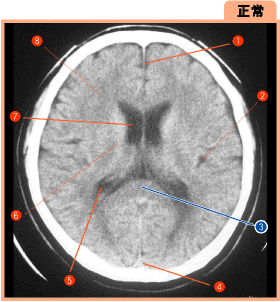

▲28ページ 正常画像内(2007/2/5)

※3の引き出し線の位置が異なっていました(下は修正済みの画像です.青線で示しています)

| ● |

▲28ページ 構造部位の名称中(2007/2/5)

※3番と5番が入れ替わっておりました

| × |

3脈絡叢(choroid plexus) 5脳梁膨大部(splenium) |

3脳梁膨大部(splenium) 5脈絡叢(choroid plexus) |

▲28ページ 構造部位の名称中(2006/12/25)

※6番と7番が入れ替わっておりました

6 側脳室体部(body of lateral ventricle) 7 尾状核体部(body of caudate nucleus) |

6 尾状核体部(body of caudate nucleus) 7 側脳室体部(body of lateral ventricle) |